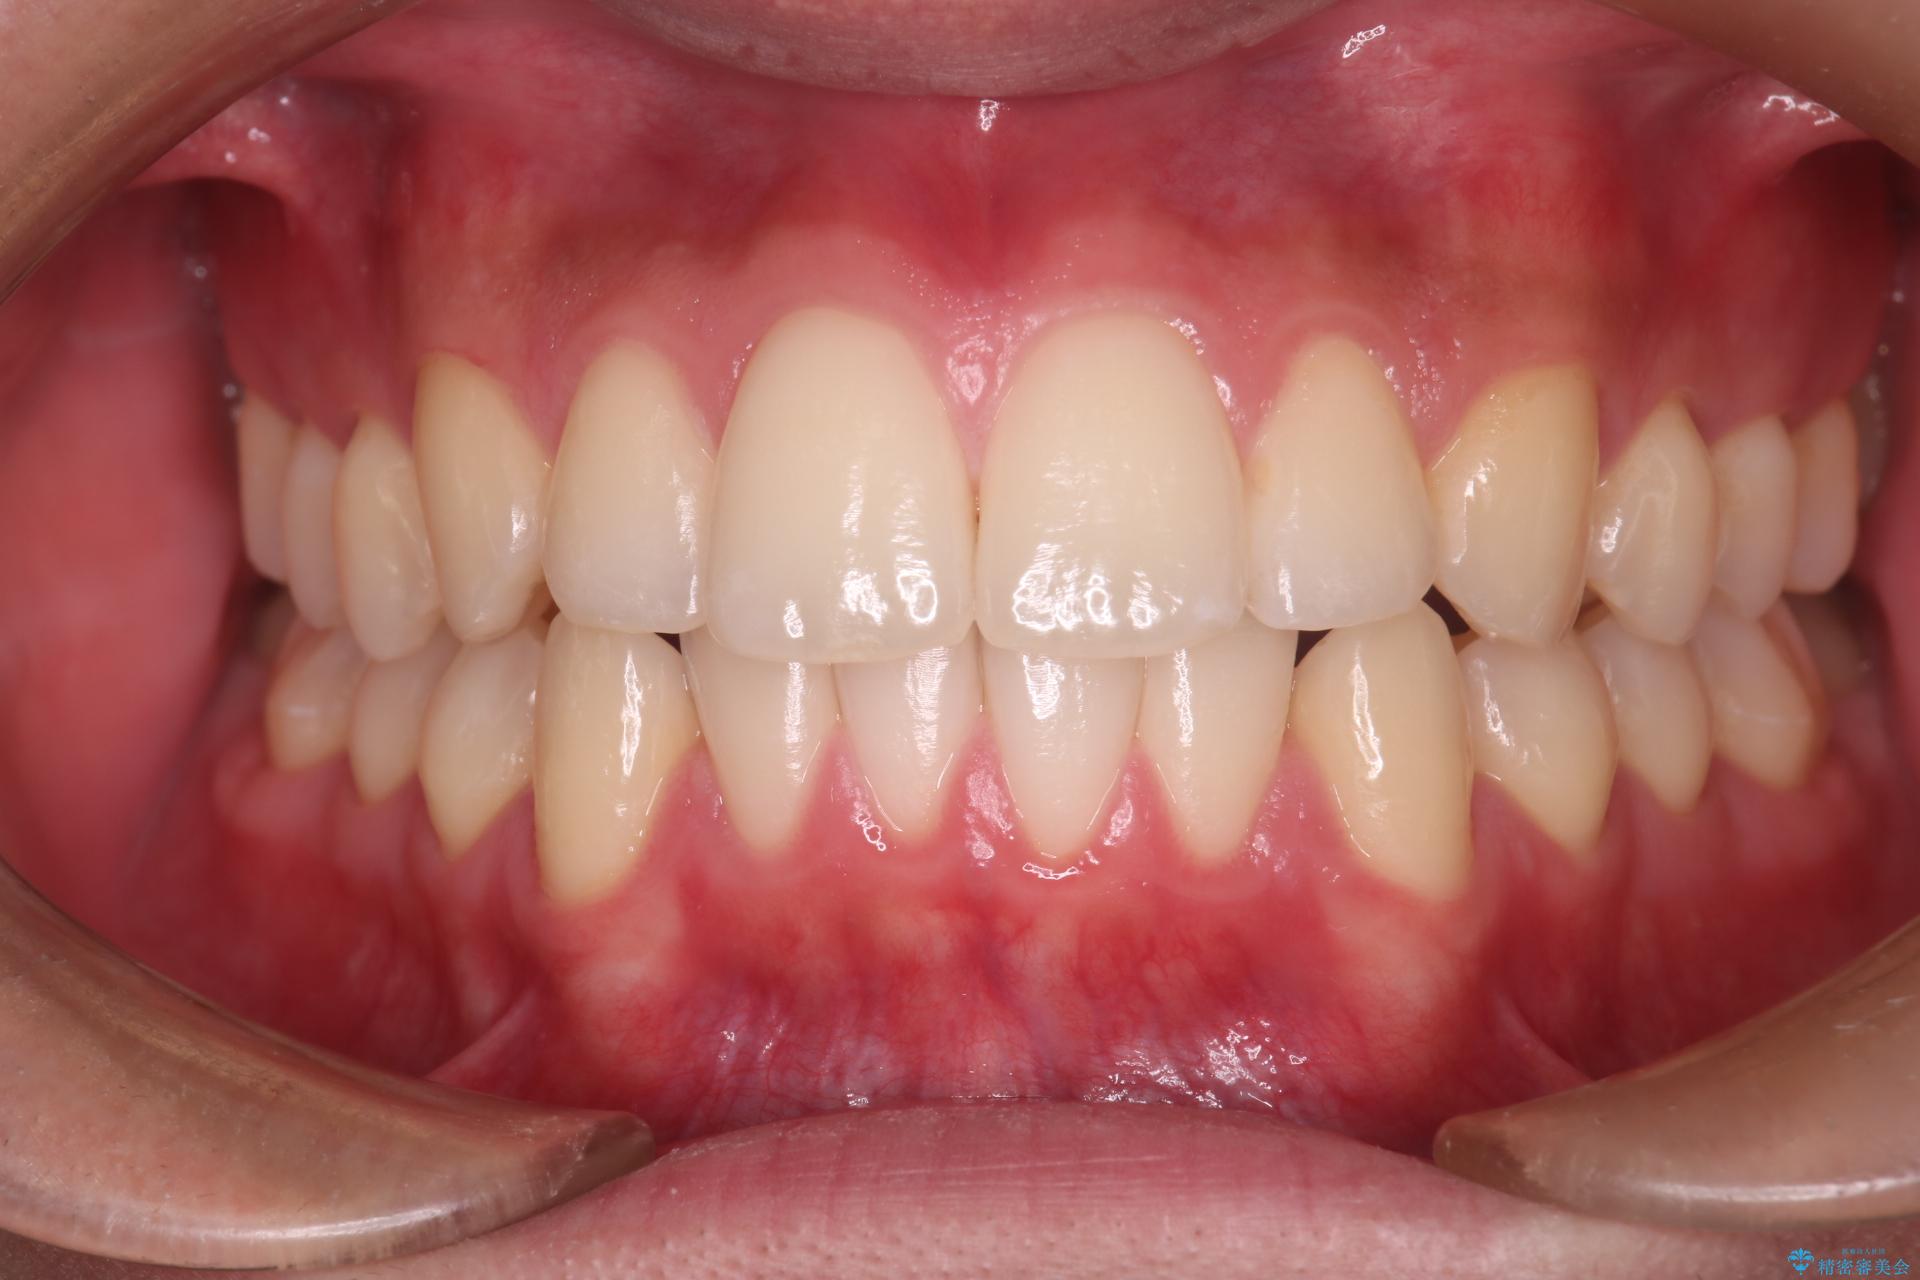

上の前歯が出ているのが気になるとご来院された患者様です。

治療後について